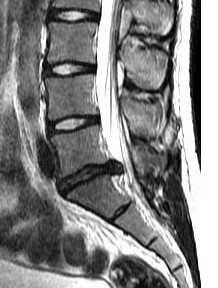

(Справа) Т2-ВИ, сагиттальный срез: различные аспекты дегенеративного поражения межпозвонковых дисков, включающие грыжи Шморля нижних замыкательных пластинок L3 и Т12, диффузную дегенерацию дисков на различных уровнях со снижением их высоты, выраженный стеноз спинномозгового канала на нескольких уровнях вследствие протрузий межпозвонковых дисков и гипертрофии связок. (Слева) Микрофотограмма (окраска гематоксилином и эозином): признаки выраженных дегенеративных изменений диско вертебрального перехода в виде дегенерации замыкательной пластинки с разрушением хряща, образования полостей в пульпозном ядре, формирования очагов грануляционной ткани и грыжевых дефектов в хрящевом слое замыкательной пластинки.